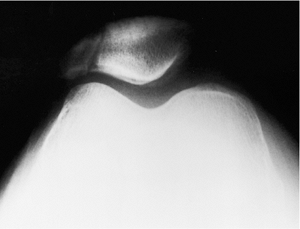

following injury include anteroposterior (AP), lateral, and axial views

of the patella. A supine AP radiograph is obtained, centered over the

patella (Fig. 24.1). The lateral radiograph can

be taken as a cross-table lateral, with the knee slightly flexed. For

an axial view, a Merchant’s view is most easily and safely obtained in

the injured patient (Fig. 24.2). The patient is

placed supine on the x-ray table with the knee flexed 45 degrees over

the end of the table. The x-ray beam is angled at 30 degrees from the

horizontal, and the cassette is placed perpendicular to this x-ray beam

1 foot below the knee. Comparison views of the uninjured knee can be

helpful in selected patients (i.e., those with a bipartite patella).

Figure 24.2.

Axial view of the patella showing a vertical fracture of the lateral facet of the patella. There is minimal displacement of the fragments. |